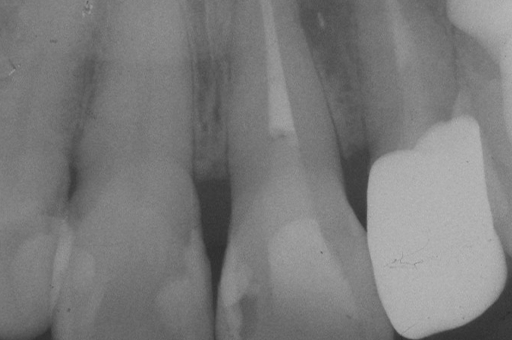

精密根管治療におけるリスク

- 根の治療を開始して初めて認識する事実、歯根内部の穿孔、歯根の破折などが存在する場合、治療の成功率は低下いたしますが、できる限りの対応はさせていただきます。

- 治療中リーマー破折の可能性がございます。その場合には最大限対応しますが、除去できない場合もございます。

万一、除去できず、問題がある場合には、外科的に歯根端切除術を行う場合がございます。 - 根の治療の中断により、再び細菌感染を起こし、再治療の必要性が生じる場合がございますので必ず予約日にご来院ください。

- 再根管治療の場合(一度でも根管治療を行った歯)は根管内が細菌により汚染されています。根管内の汚れをきれいにしていくと根管壁が薄くなるため強固に硬化し、持続的な殺菌作用を持つ特殊なセメント(MTAセメント)で充填する場合があります。MTAセメントを使用することにより、条件の悪い歯でも保存が可能な場合があります。治療の過程で判断致しますので、必要な場合は別途料金が発生致します。